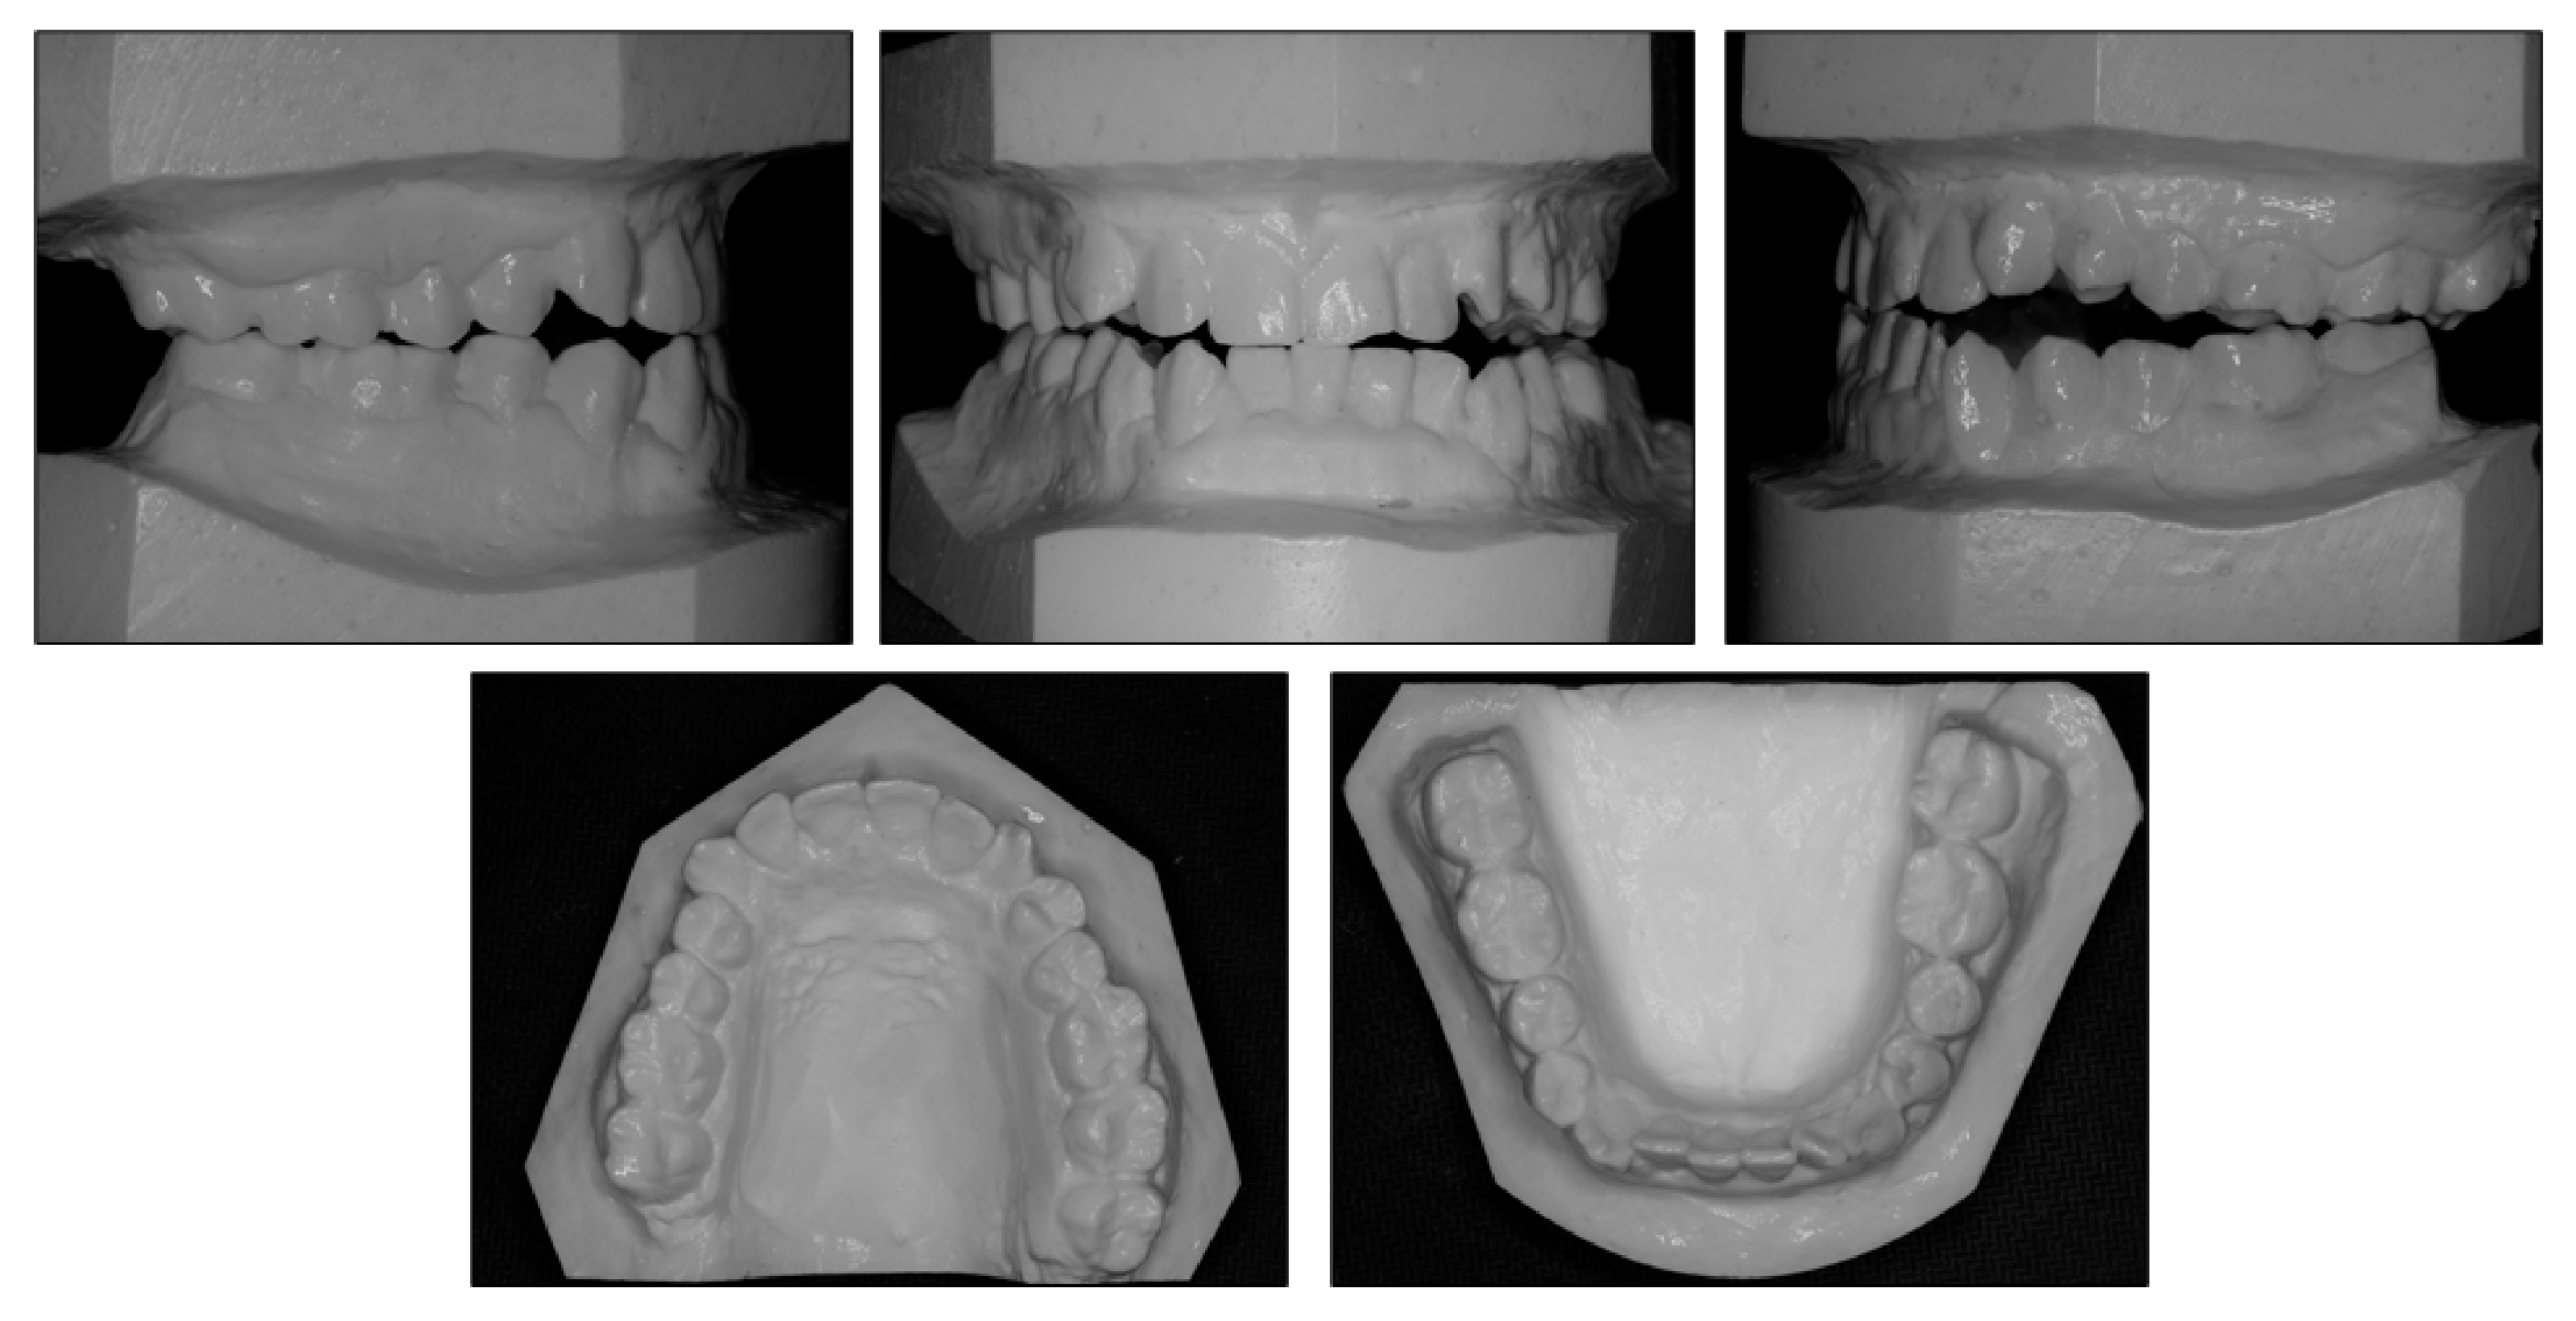

Figure 2.

Pretreatment models.

Intraorally, the patient had Class III molar and canine relationship on the right side and Class I molar and canine relationship on the left side (Figure 2). The overbite was almost zero and the overjet was −0.8 mm. There was lateral openbite on both sides, which was more severe on the left side including the canines and premolars. The mandibular left canine, premolars and first molar were in crossbite. The upper dental midline was deviated 1 mm to the right side and the lower dental midline shifted 4 mm to the left side. There was mild crowding in both arches.